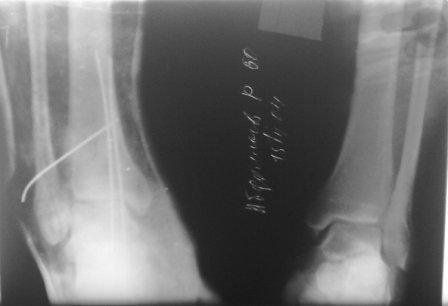

Уважаемые коллеги. Б. 61 г. травму получил 1 мес.назад. В одном мед.учрежд. произведена закрытая репозиция, фиксация спицами - учитывая большой риск не оперирован ( сахарный диабет, 2 тип. несколько инфарктов, состояние п/о А.К.Ш.).

Сейчас вот такая картина. Прежних снимков пока нет, обещали найти.

Понимаю, что надо 1/3 трубчатая пластина, и позиционный винт, возможно придется восстановить перед.межберцов.связку. Но риск очень большой, сам б-ной сильно боится операции.